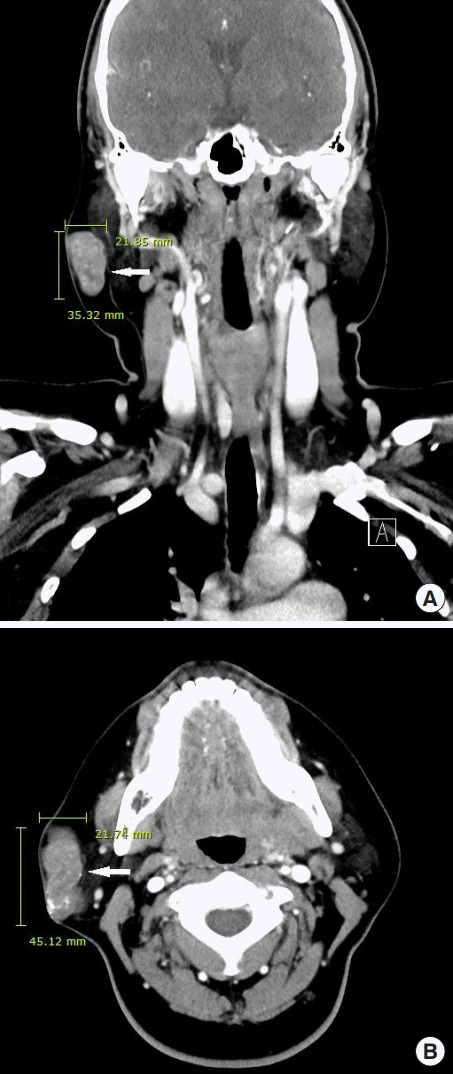

诊断时为35岁的张雨绮(女,化名)右侧腮腺区有肿块,就诊于佳学基因检测合作医院的整形外科。 肿块直径约 1 cm,张雨绮因无临床症状而拒绝手术切除。 然而,在怀孕的中晚期,肿块的大小增加到 5 厘米(图 1),并且变得疼痛。 分娩后肿块停止生长。 触诊肿块时,患者报告疼痛从腮腺区放射至耳后区。 病灶摸起来温暖、坚硬、淡蓝色和分叶状。 由于临床症状加重,患者同意接受手术切除肿块。

毛母质瘤是一种良性皮肤肿瘤,起源于分化为毛母质细胞的表皮原始基底细胞。 大多数毛母质瘤的直径约为 1 厘米,而直径为 5 厘米或以上的则被归类为巨大毛母质瘤。 头颈部毛母质瘤的鉴别诊断包括皮脂腺囊肿、骨化性血肿、鳃残余、耳前窦、淋巴结肿大、巨细胞瘤、软骨瘤、皮样囊肿、退化性纤维黄瘤、异物反应、皮肤骨瘤。 准确诊断毛母质瘤需要放射影像学和组织病理学检查。 其组织病理学特征包括外围的细胞簇(包括有核基底样细胞)和中心的无核影细胞(也称为“鬼细胞”)呈圆形排列。 巨大的毛母质瘤通常与外伤有关,并且有时会在外伤事件后观察到溃疡或坏死组织物质的局灶性经表皮消除。